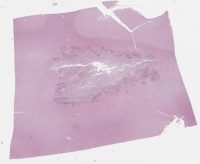

AANP2006-10.svs

42035 x 33377

@ 20X